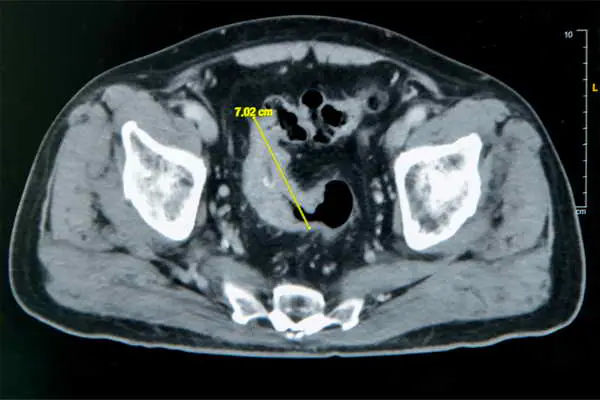

大腸直腸外科主任張譽耀醫師表示,老翁罹患乙狀結腸癌,腫瘤約7公分造成腸子幾乎完全阻塞,也導致老翁一進食就會肚子又脹又痛;術前因為不敢進食,老翁體重下降、營養不足,也可能造成傷口癒合不良。老翁的手術其實會有兩個傷口,一個是肚子上的傷口、一個腸子的傷口,若腸子傷口癒合不良會造成腸吻合滲漏,到時就必須做人工肛門了!所幸經過提早住院,透過靜脈營養針先建立營養,讓病人強健身體後才手術,術後傷口果然順利癒合。手術順利完成,老翁術後恢復良好,疼痛程度遠低於預期,他開心表示:「沒想到這麼快就能下床,真的很感謝醫師。」

圖文:雲林七旬翁便秘竟是7 公分大腸癌,彰基單孔達文西SP手術助順利除癌。